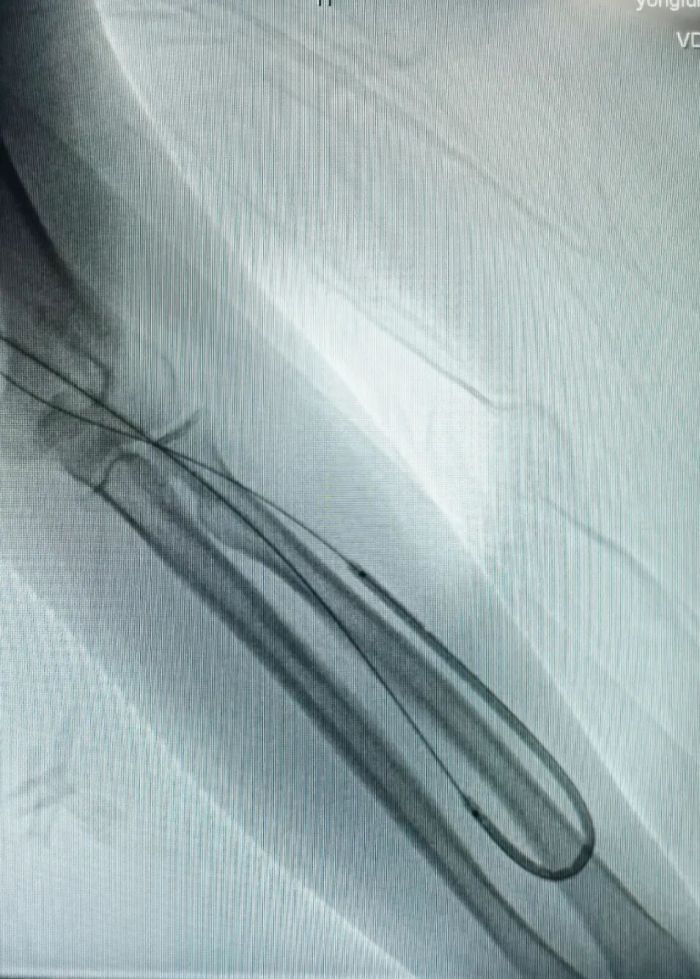

术中2.jpg术中影像